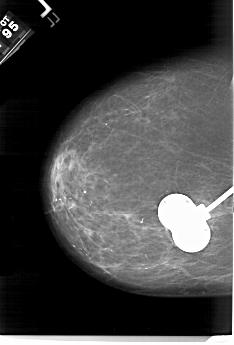

A_1532_1.RIGHT_CC

RIGHT_CC LINES 6676 PIXELS_PER_LINE 4426 BITS_PER_PIXEL 12 RESOLUTION 43.5 OVERLAY

FILE: A_1532_1.RIGHT_CC.OVERLAY

TOTAL_ABNORMALITIES 1

ABNORMALITY 1

LESION_TYPE MASS SHAPE OVAL MARGINS ILL_DEFINED

ASSESSMENT 4

SUBTLETY 3

PATHOLOGY MALIGNANT

TOTAL_OUTLINES 1

BOUNDARY